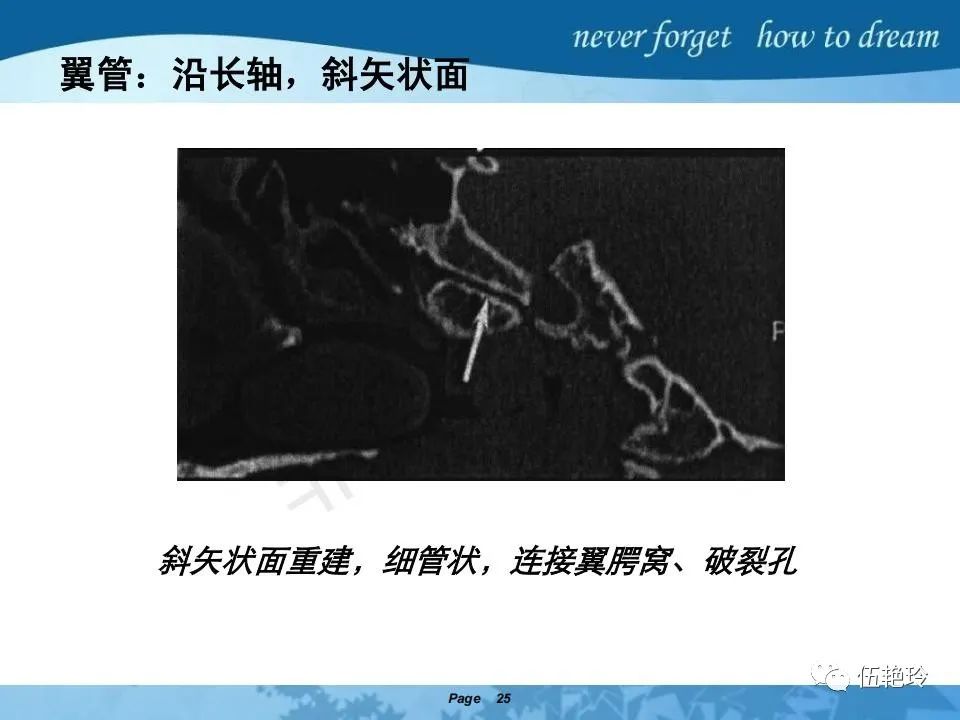

翼腭窝的解剖结构与鼻咽癌侵犯

2.31 向上颅内:①鼻咽顶壁→破裂孔(岩尖、斜坡)→蝶窦、海绵窦;②鼻咽顶壁→蝶骨基底部→蝶窦、海绵窦;③鼻咽侧壁→茎突前间隙→蝶骨大翼(卵圆孔)→海绵窦;④鼻咽侧壁→茎突前间隙→翼腭窝→ 颞下窝;⑤鼻咽前壁→鼻腔→翼突、翼腭窝→眶下裂→眶尖→海绵窦;⑥鼻咽前壁→鼻腔→上颌窦、筛窦;